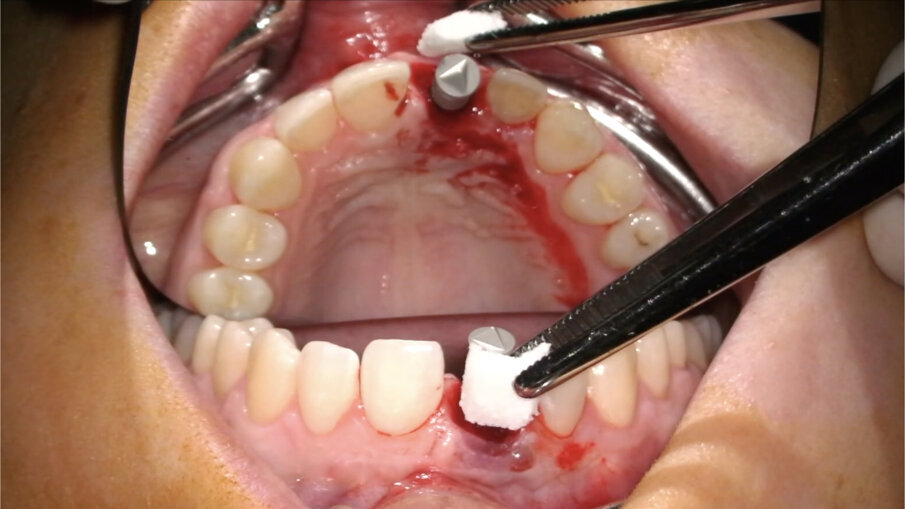

Non vanno eseguite incisioni di scarico in quanto non sono necessarie (Fig. 13). Diversamente, nei casi di edentulia parziale frontale deve essere eseguita un’incisione vestibolare (Fig. 14) a partenza intra-sulculare dai denti adiacenti. Come noto, tale incisione non deve coinvolgere la parte coronale delle papille: l’interessamento dei picchi ossei, infatti, porterebbe inevitabilmente alla perdita di 1-1,5 mm di osso con compromissione dell’estetica finale. In entrambi i casi, al fine di posizionare una matrice in collagene, verrà eseguita un’incisione a spessore parziale creando una piccola tasca mucosa corrispondente alla porzione buccale della zona trattata (Fig. 15).

- Posizionamento della matrice e sutura

La matrice va posizionata nella tasca mucosa creata in precedenza (Fig. 22). Nel caso in cui siano state eseguite incisioni, i tessuti molli devono essere ermeticamente suturati sopra di essa, mentre, nel caso opposto, deve essere delicatamente inserita in modo tale da sommergerla completamente.

Fig. 15_Incisione verticale per la creazione della tasca mucosa a spessore parziale.

Fig. 22_Posizionamento della matrice in collagene.